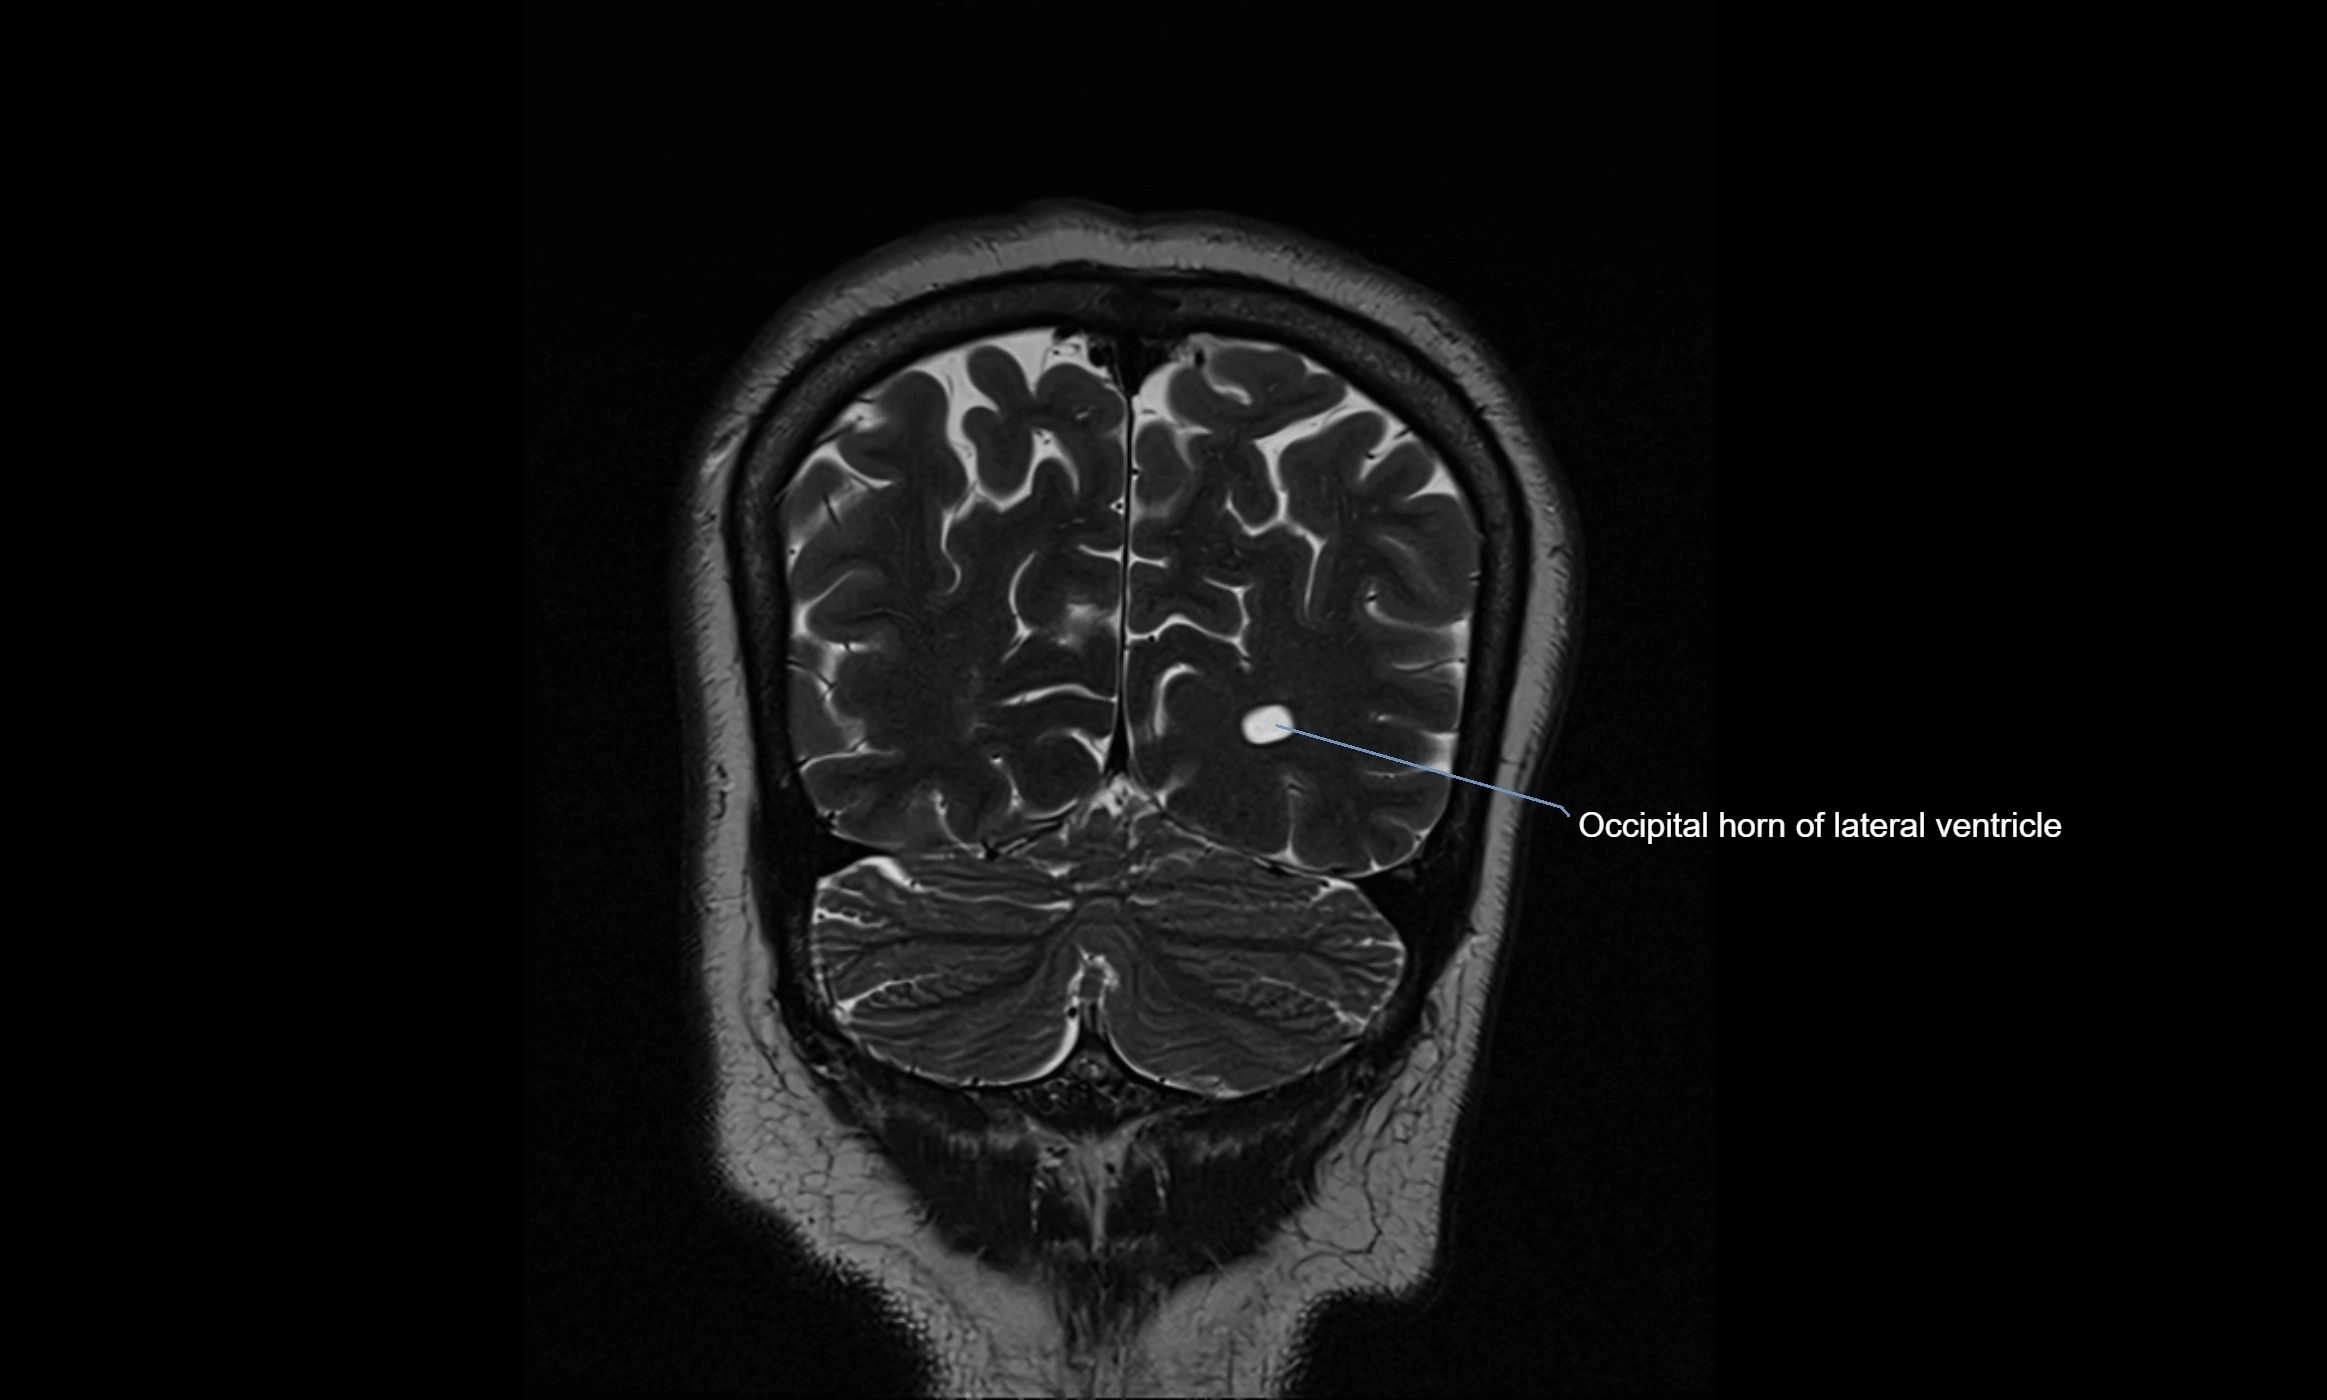

MRI images

image